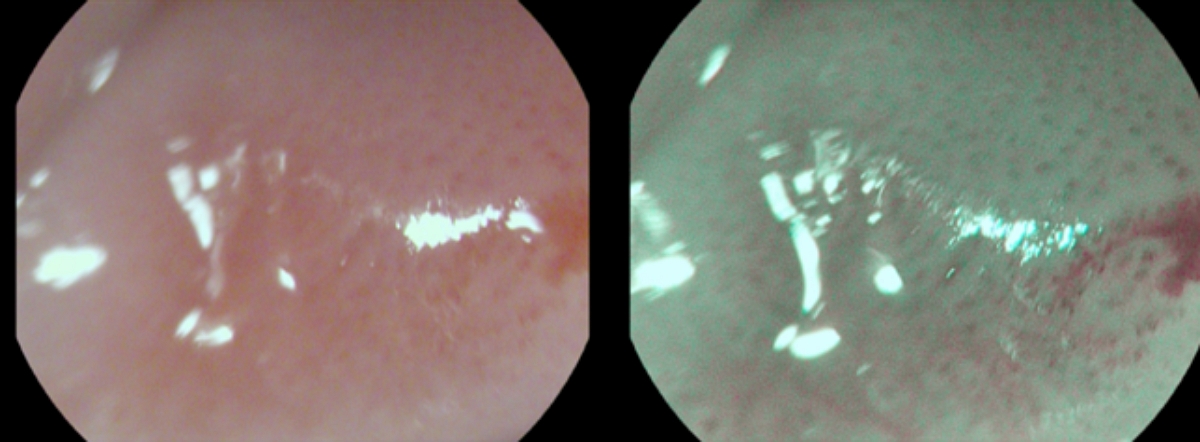

Рис. 1A. Шаг 1: выявление и макроскопическая оценка патологического очага в режиме двойного изображения в узком спектре на примере папилломы пищевода. Как видно из данного рисунка – визуализируется доброкачественное эпителиальное новообразование до 0,5 см с четкими контурами, однородной окраски.

Fig. 1A. Identification and macroscopic assessment of a pathological focus in the double image mode in a narrow spectrum by example esophageal papillomas. As can be seen from this figure, a benign epithelial neoplasm up to 0.5 cm with clear contours and uniform color is visualized.

Пациентка С., 60 лет. Поступила на плановое обследование в связи с жалобами на дискомфорт в эпигастральной области, не связанный с приемом пищи. При проведении ЭГДС в ср/3 пищевода диагностировано эпителиальное новообразование на широком основании до 0,5 см, тип 0-1s по Парижской классификации. Результаты работы алгоритма представлены в виде визуализированных шагов по выявлению и макроскопической оценке патологического очага в режиме двойного изображения в узком спектре (рис. 1 (A-G). Проведена детальная оценка границ, микроструктуры, ангиоархитектоники, определен предположительный тип морфологической структуры патологического очага, осуществлен выбор тактики эндоскопического хирургического лечения в режиме узкого спектра с оптическим увеличением в 136 раз (рис. 1В).